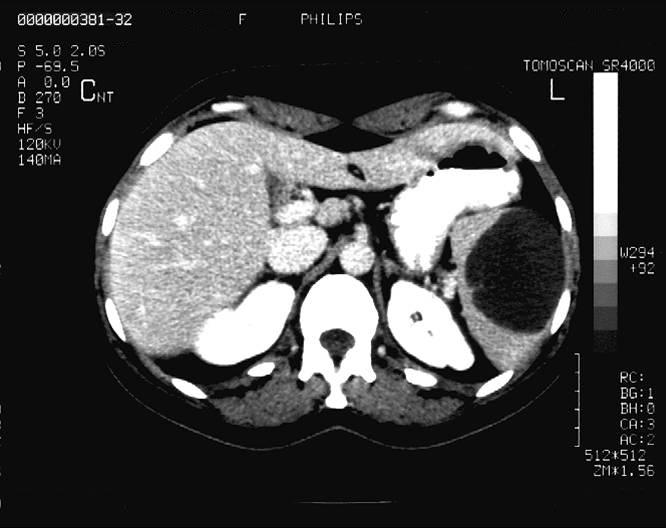

Their US apperarences include mostly an inhomogeneous, hyperechoic or hypoechoic lesion, which is arterially hypervascularised, and several arterioportal shunts may develop. The demonstration of shunt related portal vein flow disturbance by doppler US has a prominent importance. The adjudication of the cirrhosis related HCC by ultrasound is often a particularly difficult task.

HCC appears mostly as low density on the native CT scan, with inhomogeneous structure and a sorrounding with a slightly increased density bearing capsule can be also detected. The completion of the three-phase CT scan (arterial, venous, late) is especially important in case of a suspicion of HCC. The appearance of the inhomogeneous lesion in the arterial phase, including sometimes non contrast enhancing necrotic areas inside, bears with a diagnostic value. The capsule can be detected best in the venous phase.

Concerning the HCC, the knowledge of history is very important for the decision and usually the oncoteams consider the performance of an imaging modality guided biopsy basically important for the further therapeutic decisions (because of the hystological validation rather core biopsy should be performed! (Figure 26, 27, 28).

Figure 26: HCC, verified with FNAB, US

Figure 27: HCC, TAE, agniography

Figure 28: HCC, native CT after TAE